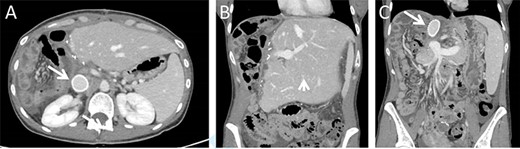

Surgical exploration via right subcostal incision with midline extension was performed. A giant tumour encompassing the entire right lobe including the middle hepatic vein as well as the caudate lobe and retrohepatic IVC was demonstrated. Femoral-Jugular venous–venous bypass was used during an en-bloc resection of the right hemi-liver, most of segment four, the caudate lobe, and approximately a 10 cm section of the retrohepatic IVC (Fig. 2). Reconstruction of the IVC was performed using a 20 mm Gore-tex graft (Fig. 2). A 20-minute bypass time was required. The surgery went uneventful with minimal blood loss. No blood products were administered during the operations.

Intraoperative images. Intraoperative image depicting the remnant left lateral segment drained by the left hepatic vein into the IVC stump, marked by an arrow (A), and following IVC reconstruction with Gore-tex graft (B).

The immediate postoperative course was uneventful and the patient was discharged in good condition nine days following surgery. Twelve days after discharge the patient was readmitted due complaints of abdominal pain. Her vital signs, physical examination and laboratory blood indices were normal. A CT scan revealed a small amount of fluid in the abdominal cavity and thrombophlebitis of the left external iliac vein (Probably triggered by the cannula placed for venous–venous bypass). The remnant liver was markedly hypertrophied and the IVC Gore-tex graft was patent (Fig. 3).

Postoperative CT imaging. (A) Axial CT image depicting patent IVC graft (arrow). (B + C) Coronal images depicting hypertrophied remnant liver (arrowhead), patent portal vein and IVC graft (arrow).